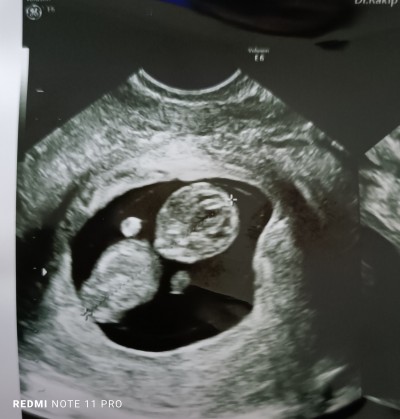

Keseye göre cinsiyer tahmini yapabile var mı

Kaç haftalık

11 hafta

Keseye göre erkek bebek canım :angel:

Bacaklar tam çıkmamış dedi doktor erkek de heralde daha erken çıkıyormuş diye duymuştum